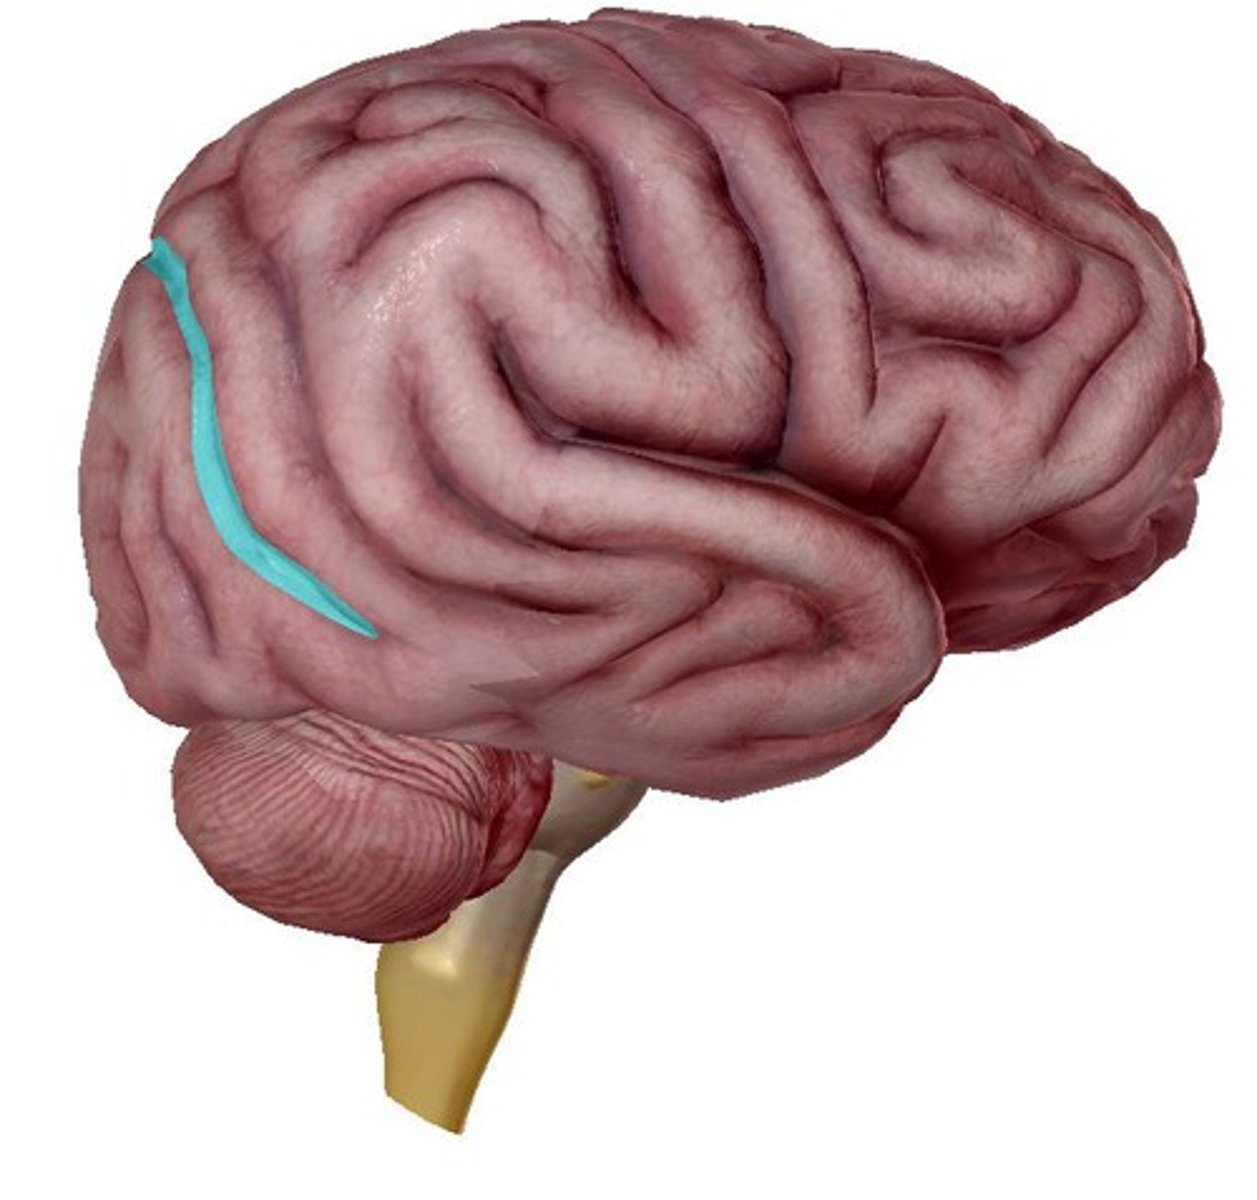

lateral cerebral sulcus

separates the frontal lobe from the temporal lobe